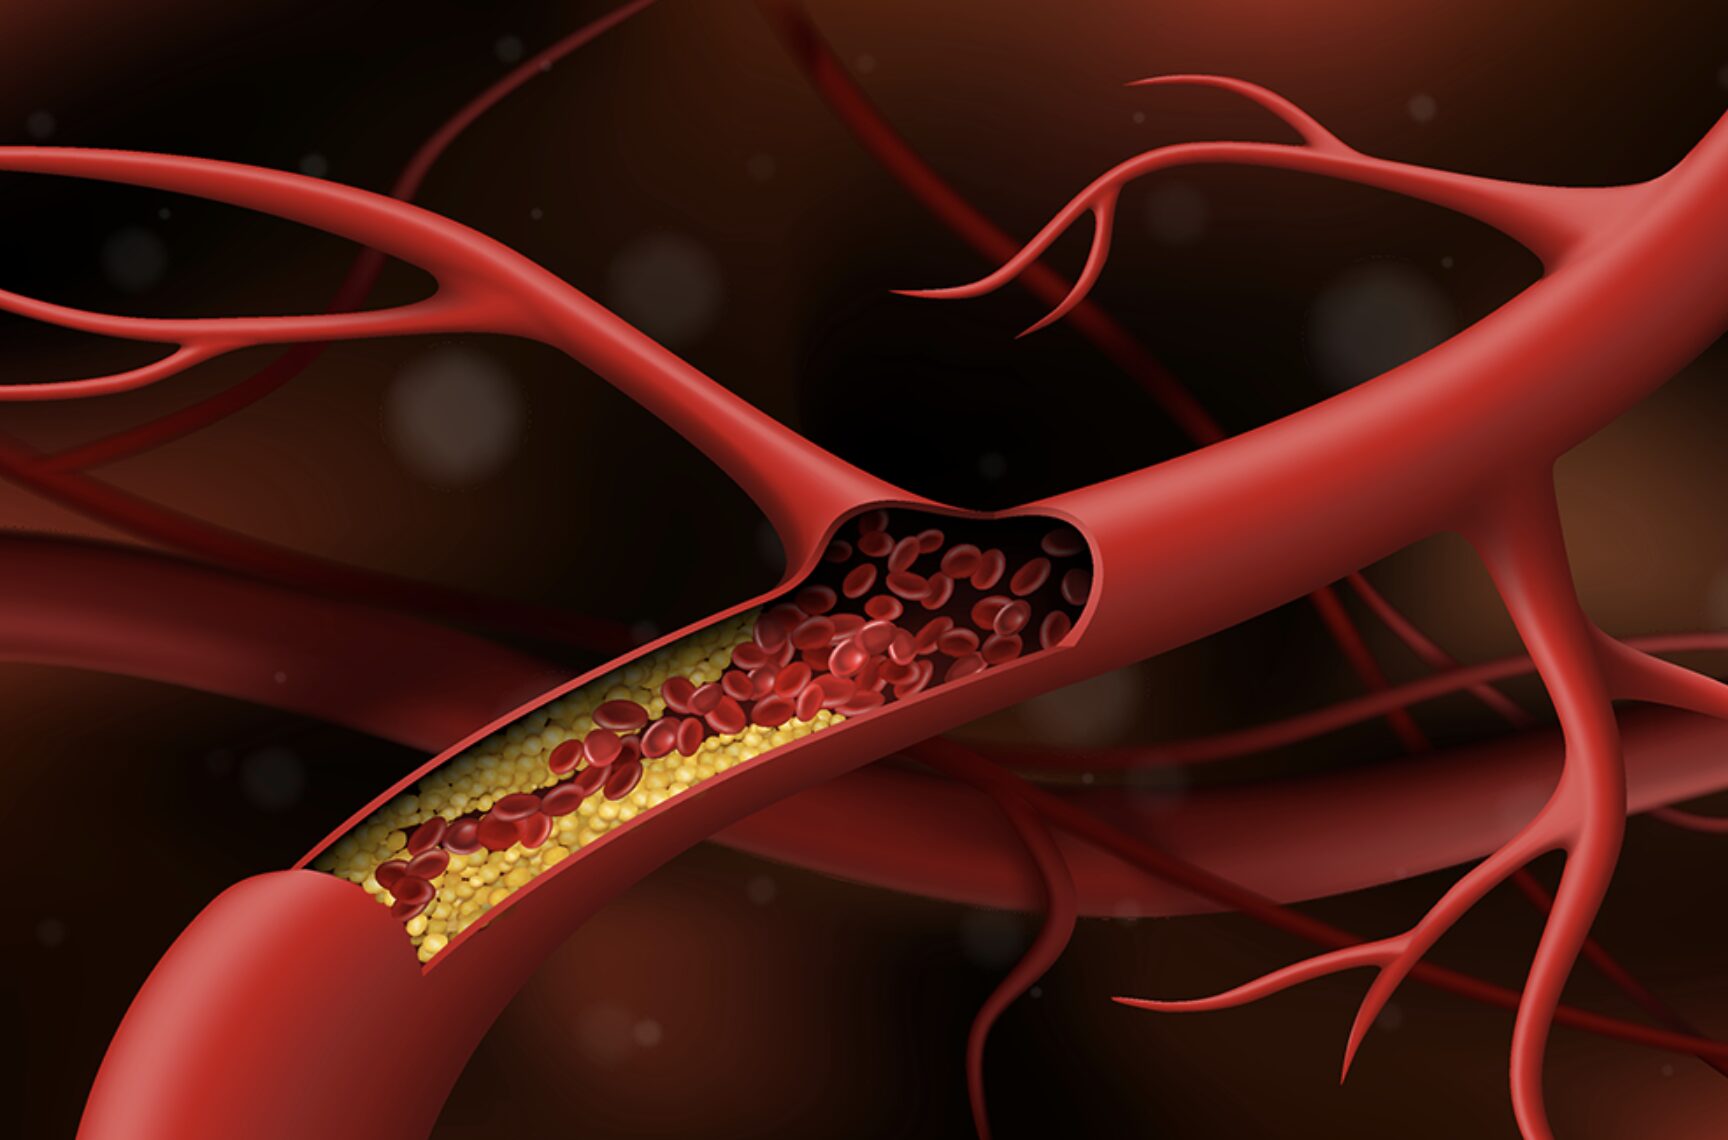

Tỷ lệ bệnh nhân đột quỵ trong thời gian đang mắc COVID-19 từ 0,9 đến 2,7%, cao gấp 7 lần so với nhiễm virus khác như influenza (cúm), song hậu COVID-19 chỉ nên khám tầm soát khi có yếu tố nguy cơ. PGS.TS.BS Nguyễn Huy Thắng, Phó chủ tịch Hội Đột quỵ Việt Nam cho biết như trên, hôm 26/3.

Sau khi khỏi COVID-19, người bệnh có thể phải đối mặt với tình trạng đột quỵ hoặc nhồi máu cơ tim. Vì vậy, việc tìm ra phương pháp phòng ngừa là mối quan tâm lớn của các F0 lành bệnh? ThS.BS Đặng Huỳnh Anh Thư – Phó Trưởng Bộ môn sinh lý, Sinh lý bệnh miễn dịch, Đại học Y dược TPHCM sẽ giúp bạn đọc giải đáp những lo lắng này.

Hậu COVID-19 làm gia tăng nguy cơ nhồi máu cơ tim, đột quỵ não

Bên cạnh các tổn thương ở phổi, các triệu chứng tim mạch cũng ghé thăm người bệnh ở giai đoạn hậu COVID-19. ThS.BS Đặng Huỳnh Anh Thư, Bộ môn Sinh lý – Sinh lý bệnh Miễn dịch, Đại học Y dược TPHCM sẽ giải đáp sâu hơn về vấn đề này trong video dưới đây.